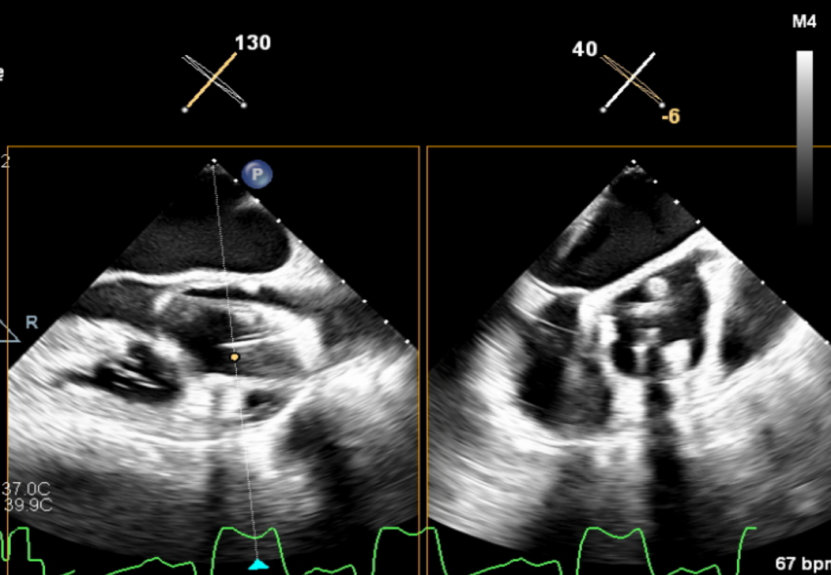

左室长轴切面可见流出道结构良好,短轴切面可见主动脉瓣大量反流。

(流出道结构观察)

(短轴切面观察)